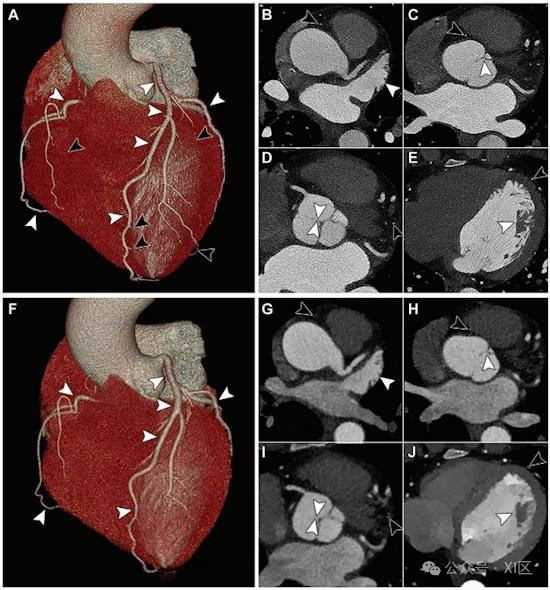

来自一位 44 岁女性的 (A-E) 冠状动脉光子计数 CT 和 (F-J) 能量积分探测器双层 CT 血管造影图像。容积渲染光子计数 CT 图像 (A) 和容积渲染能量积分探测器双层 CT 图像 (F) 显示近端冠状动脉(白色箭头),但与能量积分探测器双层 CT 相比,容积渲染和光子计数 CT 在远端冠状动脉的显示(A 中的黑色箭头)方面有明显改善。在轴位图像上,光子计数 CT 图像 (B-E) 比能量积分探测器双层 CT 图像 (G-J) 更好地描绘了梳状肌 (B, G)、主动脉瓣交界 (C, H)、无冠瓣 (D, I) 和乳头肌 (E, J)(白色箭头)。黑色箭头表示能量积分探测器双层 CT 图像上未显示的远端冠状动脉。图像来源 RSNA。